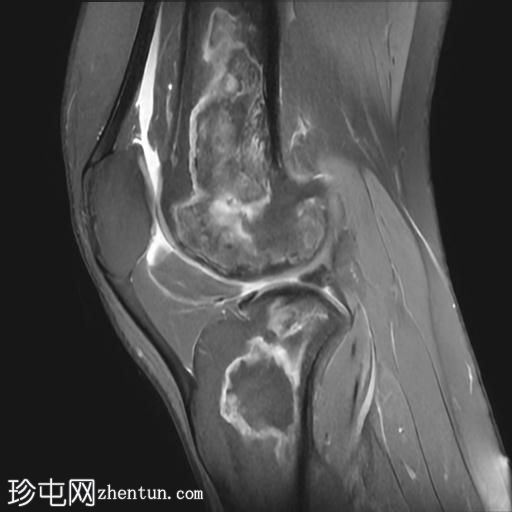

矢状位

T2加权像

在股骨远端和胫骨近端的髓腔内可见不规则的蛇形异常信号线。PD图像上,高信号线与骨髓内低信号线的内表面平行。

可见少量关节积液。

股骨远端和胫骨近端可见典型的骨梗死MRI表现。